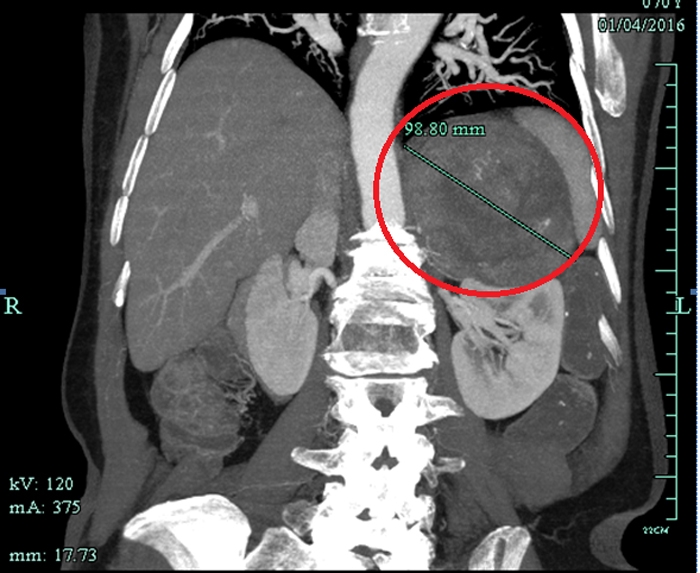

CT檢查意外發(fā)現(xiàn)巨大腫瘤

??? 原來,朱老太與高血壓相伴已經(jīng)有20多年了,一直服用降壓藥,而且血壓忽高忽低不穩(wěn)定。一個(gè)多月前,因?yàn)橹匕Y肺炎在當(dāng)?shù)蒯t(yī)院住院,行胸部CT檢查的時(shí)候發(fā)現(xiàn)左上腹有一個(gè)十多公分的巨大腫瘤。家人馬上把朱老太送到省城一家大醫(yī)院住院,磁共振檢查后考慮左腎上腺惡性腫瘤,需要做大手術(shù)。家人擔(dān)心老人瘦弱的身體承受不了開腹手術(shù),多方打聽后得知市人民醫(yī)院泌尿外科做腹腔鏡手術(shù)技術(shù)成熟,就找到了萬里軍醫(yī)師。萬醫(yī)生初步診斷為左腎上腺嗜鉻細(xì)胞瘤,考慮是惡性腫瘤,雖然腫瘤體積巨大,但能在腹腔鏡下切除腫瘤。

患者CT影像